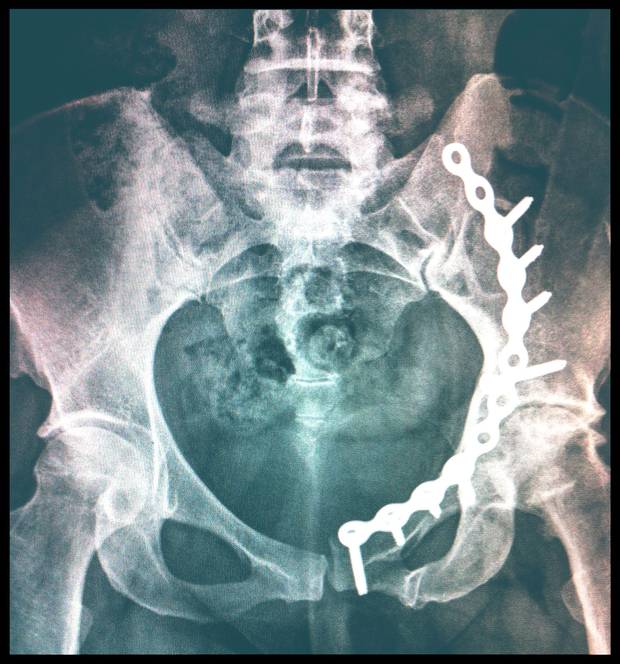

Stacey Taylor’s hip was damaged in a car accident, leaving her in a wheelchair for months. This x-ray shows the pins and metal required to hold the socket of her left hipbone together. A doctor assessing her claim for her insurance company concluded that her injuries did not warrant long-term benefits.

Ms. Taylor doesn't remember the crash in Niagara-on-the-Lake, Ont., that ended life as she knew it. Her car was broadsided, shoving her leg bone into her hip and smashing it beyond repair. That put Ms. Taylor, a federal archeologist, in a wheelchair for months, trying to walk as her hip joint deteriorated.

Pembridge Insurance started sending her to doctors, among them Dr. Platnick, to get assessed, she said, while she was still in hospital.

Her doctor said she was too young for a hip replacement at the time. As painful arthritis and other complications set in, Ms. Taylor fought to recover, exhausting her basic coverage. Pembridge then stopped paying, when she was in the middle of her treatment, because Dr. Platnick – who'd never met her – declared her injuries not serious enough to warrant long-term benefits.

Dr. Platnick had summed up reports from other assessors, also paid by Pembridge, and concluded she was not catastrophically injured – in contrast to her doctors' views. Ms. Taylor's last chance was at arbitration, where she said she limped in, using a cane. Dr. Platnick's report carried the day.

In his report on Ms. Taylor’s case, the arbitrator upholds Dr. Platnick’s findings that she was not catastrophically injured.